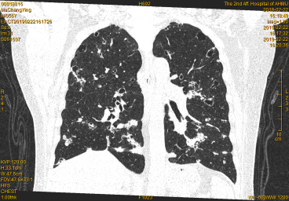

胸部CT:双肺散在结节伴部分囊样空洞样影,较老片病灶增多;双侧胸膜增厚,双侧胸腔积液。

2020.2 复查CT肺部病灶较前增多,病情进展,停用呋喹替尼治疗,治疗方案更换为替雷利珠单抗+瑞戈非尼治疗。

影像学检查结果: